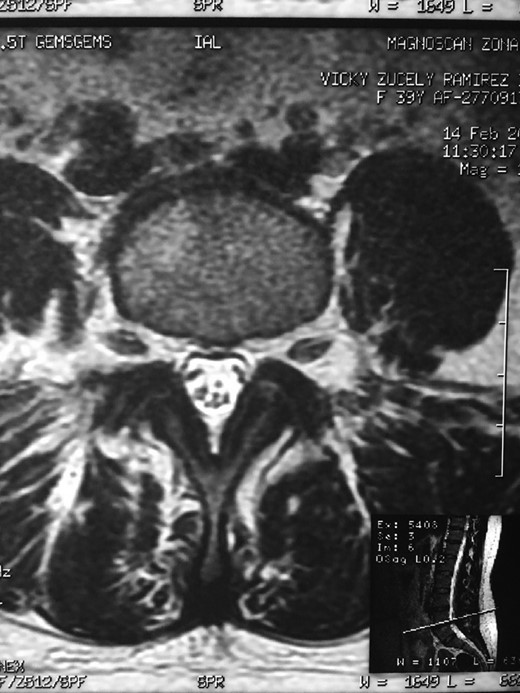

A 42-year-old female presented to the clinic with a history of chronic low back pain. She reported no relevant medical history. She had already been treated in the last 4 years by general practitioners with analgesics and home based physiotherapy with no satisfactory results. She had two previous admissions to the emergency department where morphine was prescribed to control the pain on her lower back. She was under ambulatory treatment with diclofenac, and tizanidine with partial relief of symptoms. Her main complaint was pain on the lower lumbar back with no radiation to the lower extremities. In her physical evaluation she presented limitation to full rotation and bending of the lumbar spine due to pain. Lasegue sign was negative, sensitivity, reflexes, sagittal balance, distal muscular strength and pulses were normal. Radiographs showed an overdeveloped left transverse process of the fifth lumbar vertebra which contacts with the sacrum at the left sacral wing with signs of degeneration at the same site (Fig. 1). Magnetic resonance imaging (MRI) studies were obtained (Figs 2–5). The patient was taken to the operating room where infiltration with 1 mL of lidocaine and 40 mg of Triamcinolone was performed in the pseudoarticulation between the left transverse process and the sacrum under fluoroscopic guidance. She reported a complete relief of pain after the procedure. At three months follow-up she was managed with strengthening and stabilizing exercises for the lumbar spine and postural education was initiated. She remains asymptomatic at her 12 months follow up.

Degenerative changes at the facets and disc in the adjacent segment.

The partial fusion at the lower part of the lumbosacral transition produces important alterations in normal biomechanics at the levels immediately above and below the LSTV. Changes such as hypermobility and abnormal torque moments are present at the level above the LSTV, predisposing it to early degeneration (early disc pathology and facet joint degenerative disease). Restricted movement below the LSTV produces a protective effect against degeneration of disc and facets and is related to changes (facets are smaller and coronally oriented) in the dimensions of the lower level facet joints [7]. These alterations can be verified in the adjacent levels of the LSTV in our patient.